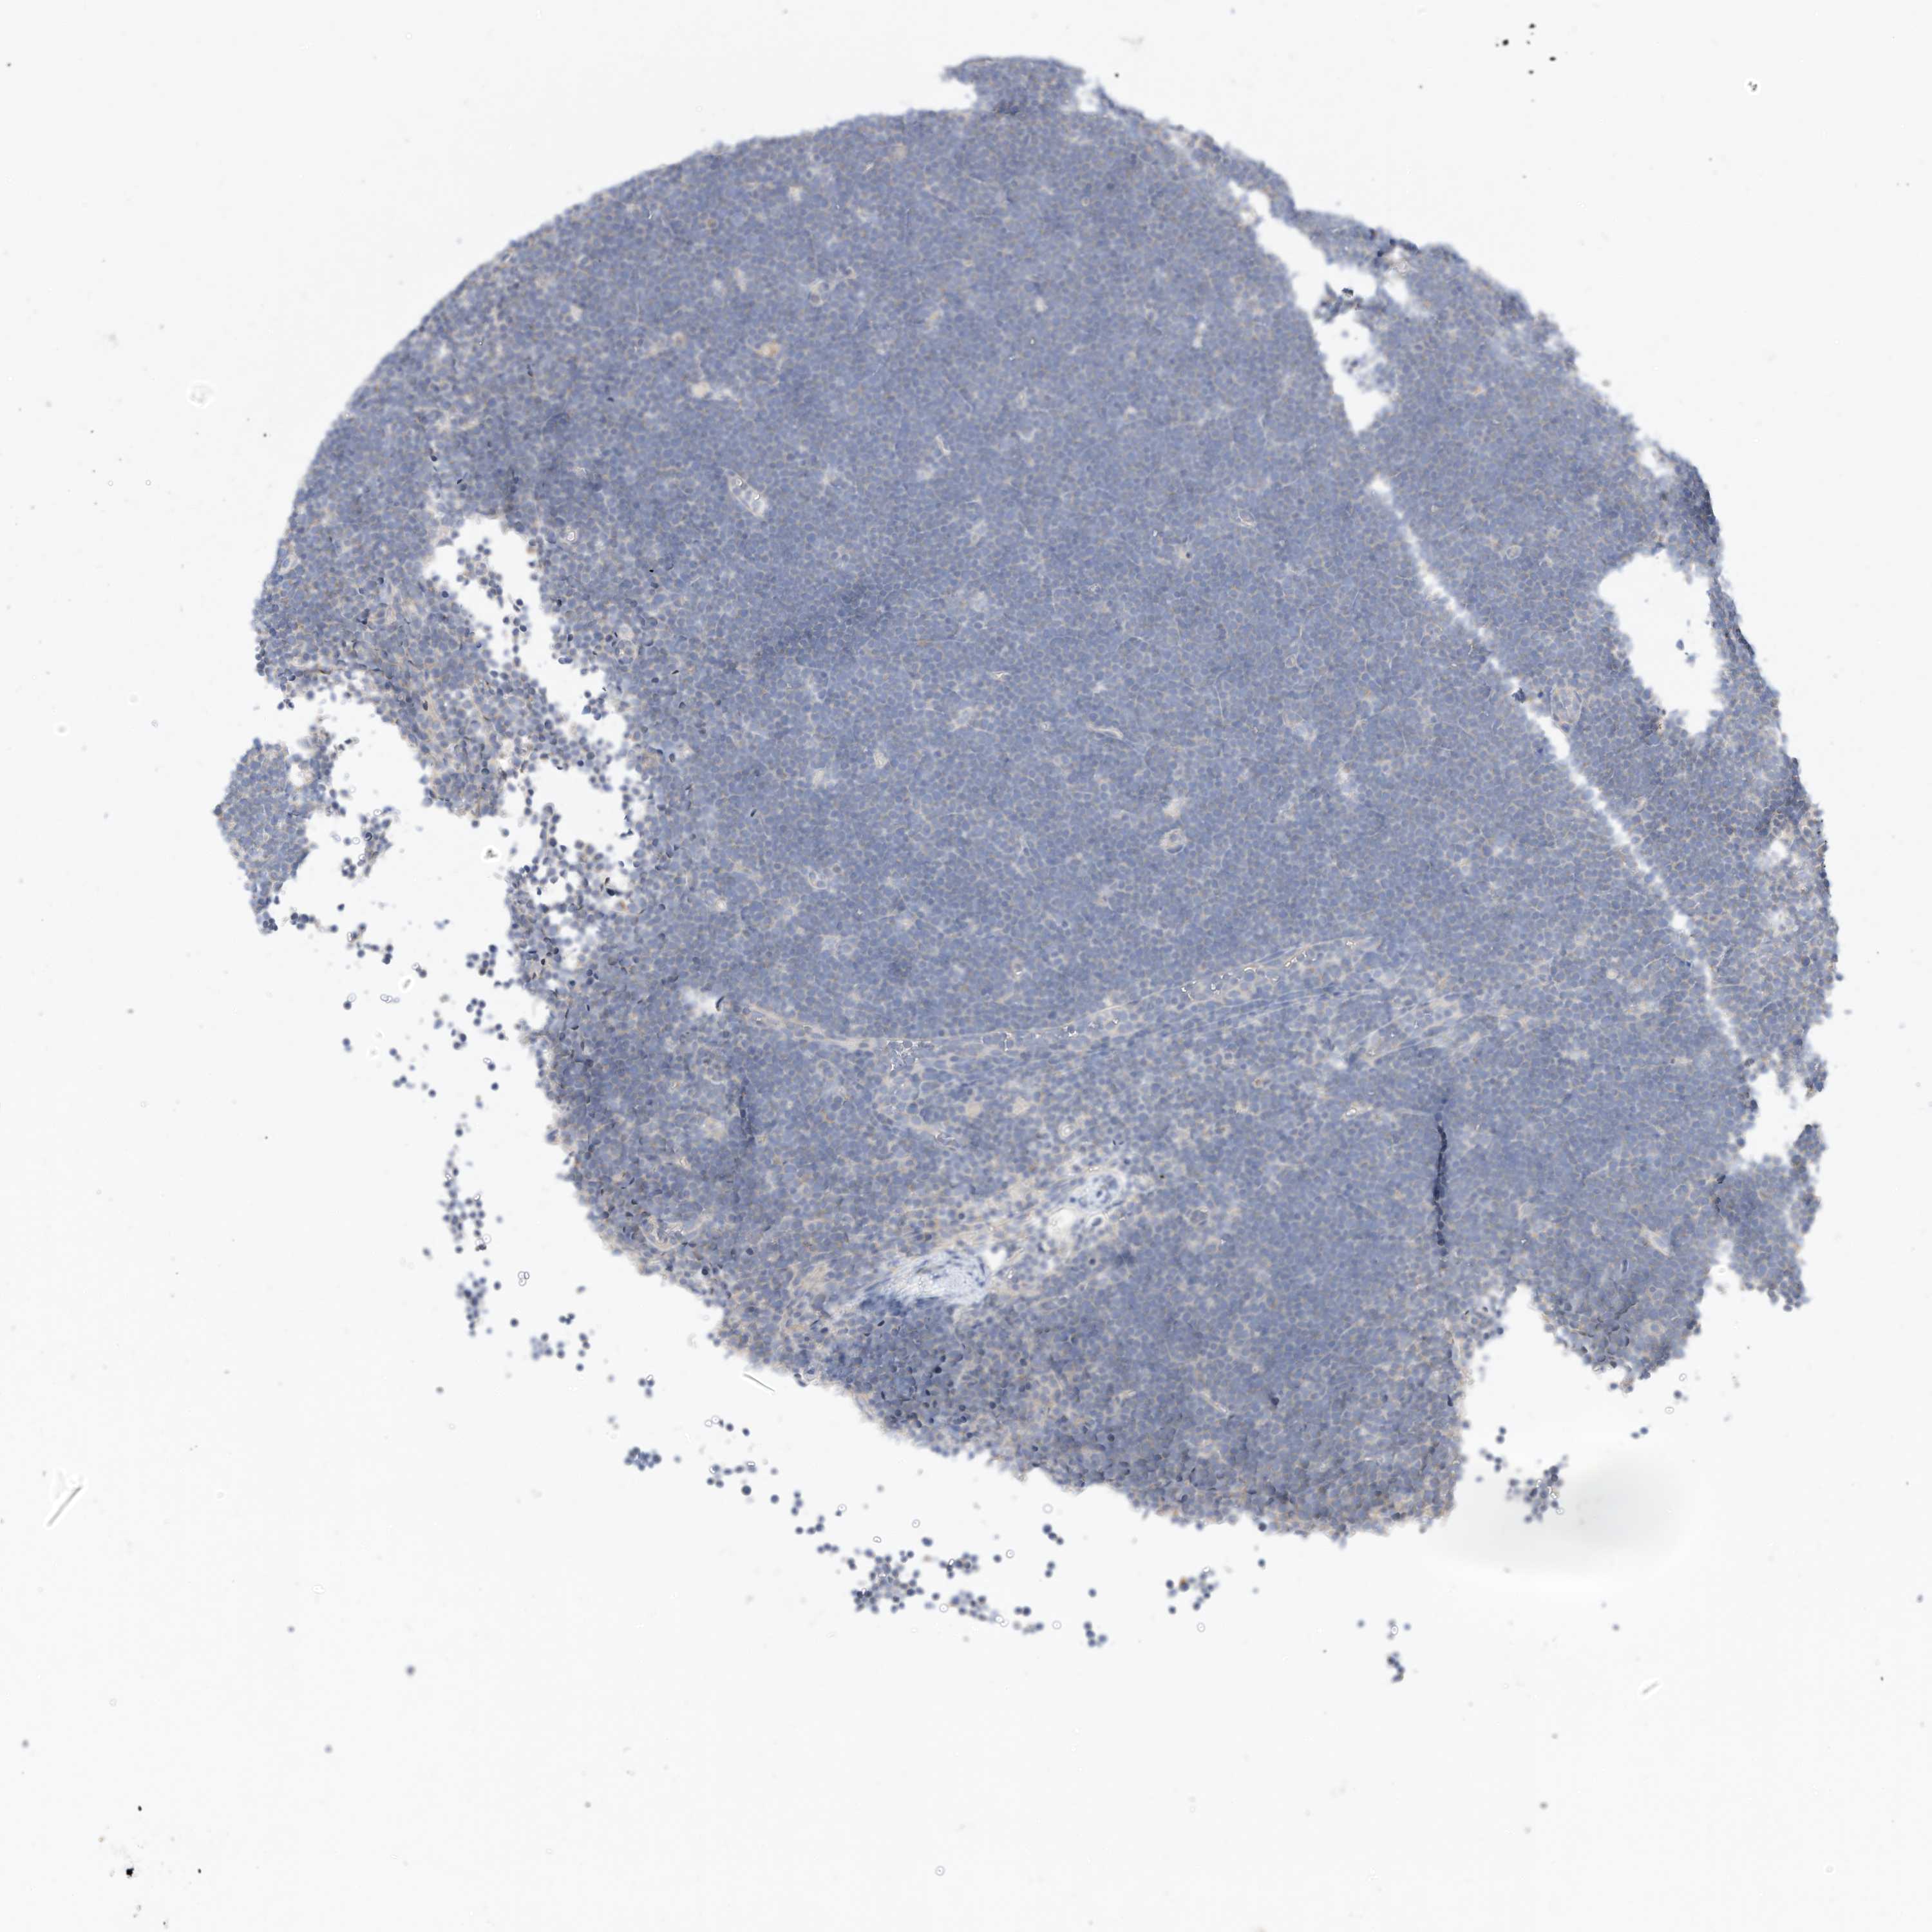

LYMPHOMA - Protein expressioni

A mouse-over function shows sample information and annotation data. Click on an image to view it in a full screen mode. Samples can be filtered based on level of antibody staining by selecting one or several of the following categories: high, medium, low and not detected. The assay and annotation is described here.

Antibody stainingi

Antibody staining in the annotated cell types in the current human tissue is reported as not detected, low, medium, or high, based on conventional immunohistochemistry profiling in selected tissues. This score is based on the combination of the staining intensity and fraction of stained cells.

Each image is clickable and will lead to virtual microscopy that enables deeper exploration of all samples and also displays staining intensity scores, fraction scores and subcellular localization as well as patient and tissue information for each sample.

Antibody HPA030345

Staining

High

Medium

Low

Not detected

Intensity

Strong

Moderate

Weak

Negative

Quantity

>75%

75%-25%

<25%

None

Location

Nuclear

Cytoplasmic/membranous

Cytoplasmic/membranous,nuclear

Hodgkin's disease, NOS

Malignant lymphoma, non-Hodgkin's type, High grade

Malignant lymphoma, non-Hodgkin's type, Low grade